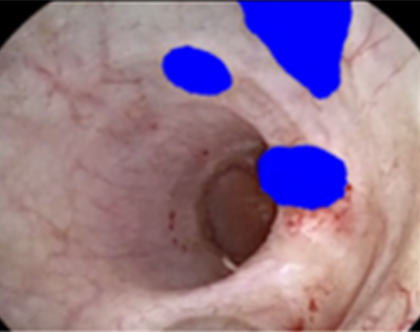

Sample Figure

Qualitative results of automated segmentation during endoscopic UTUC surgery demonstrating (left to right) the original endoscopic video image, manual segmentation performed by the surgeons (blue overlay), the contour of the automated segmentation (green overlay), and a heatmap prediction demonstrating the raw probability output per pixel. Blue and red colored pixels represent low and high probability of correct segmentation, respectively. a) Digital scope tumor identification, b) area of ablated tumor, c) fiberoptic scope tumor identification, d) example of model performing in instance with decreased visibility during tumor ablation. *Area of hemorrhage obstructing target tissue.